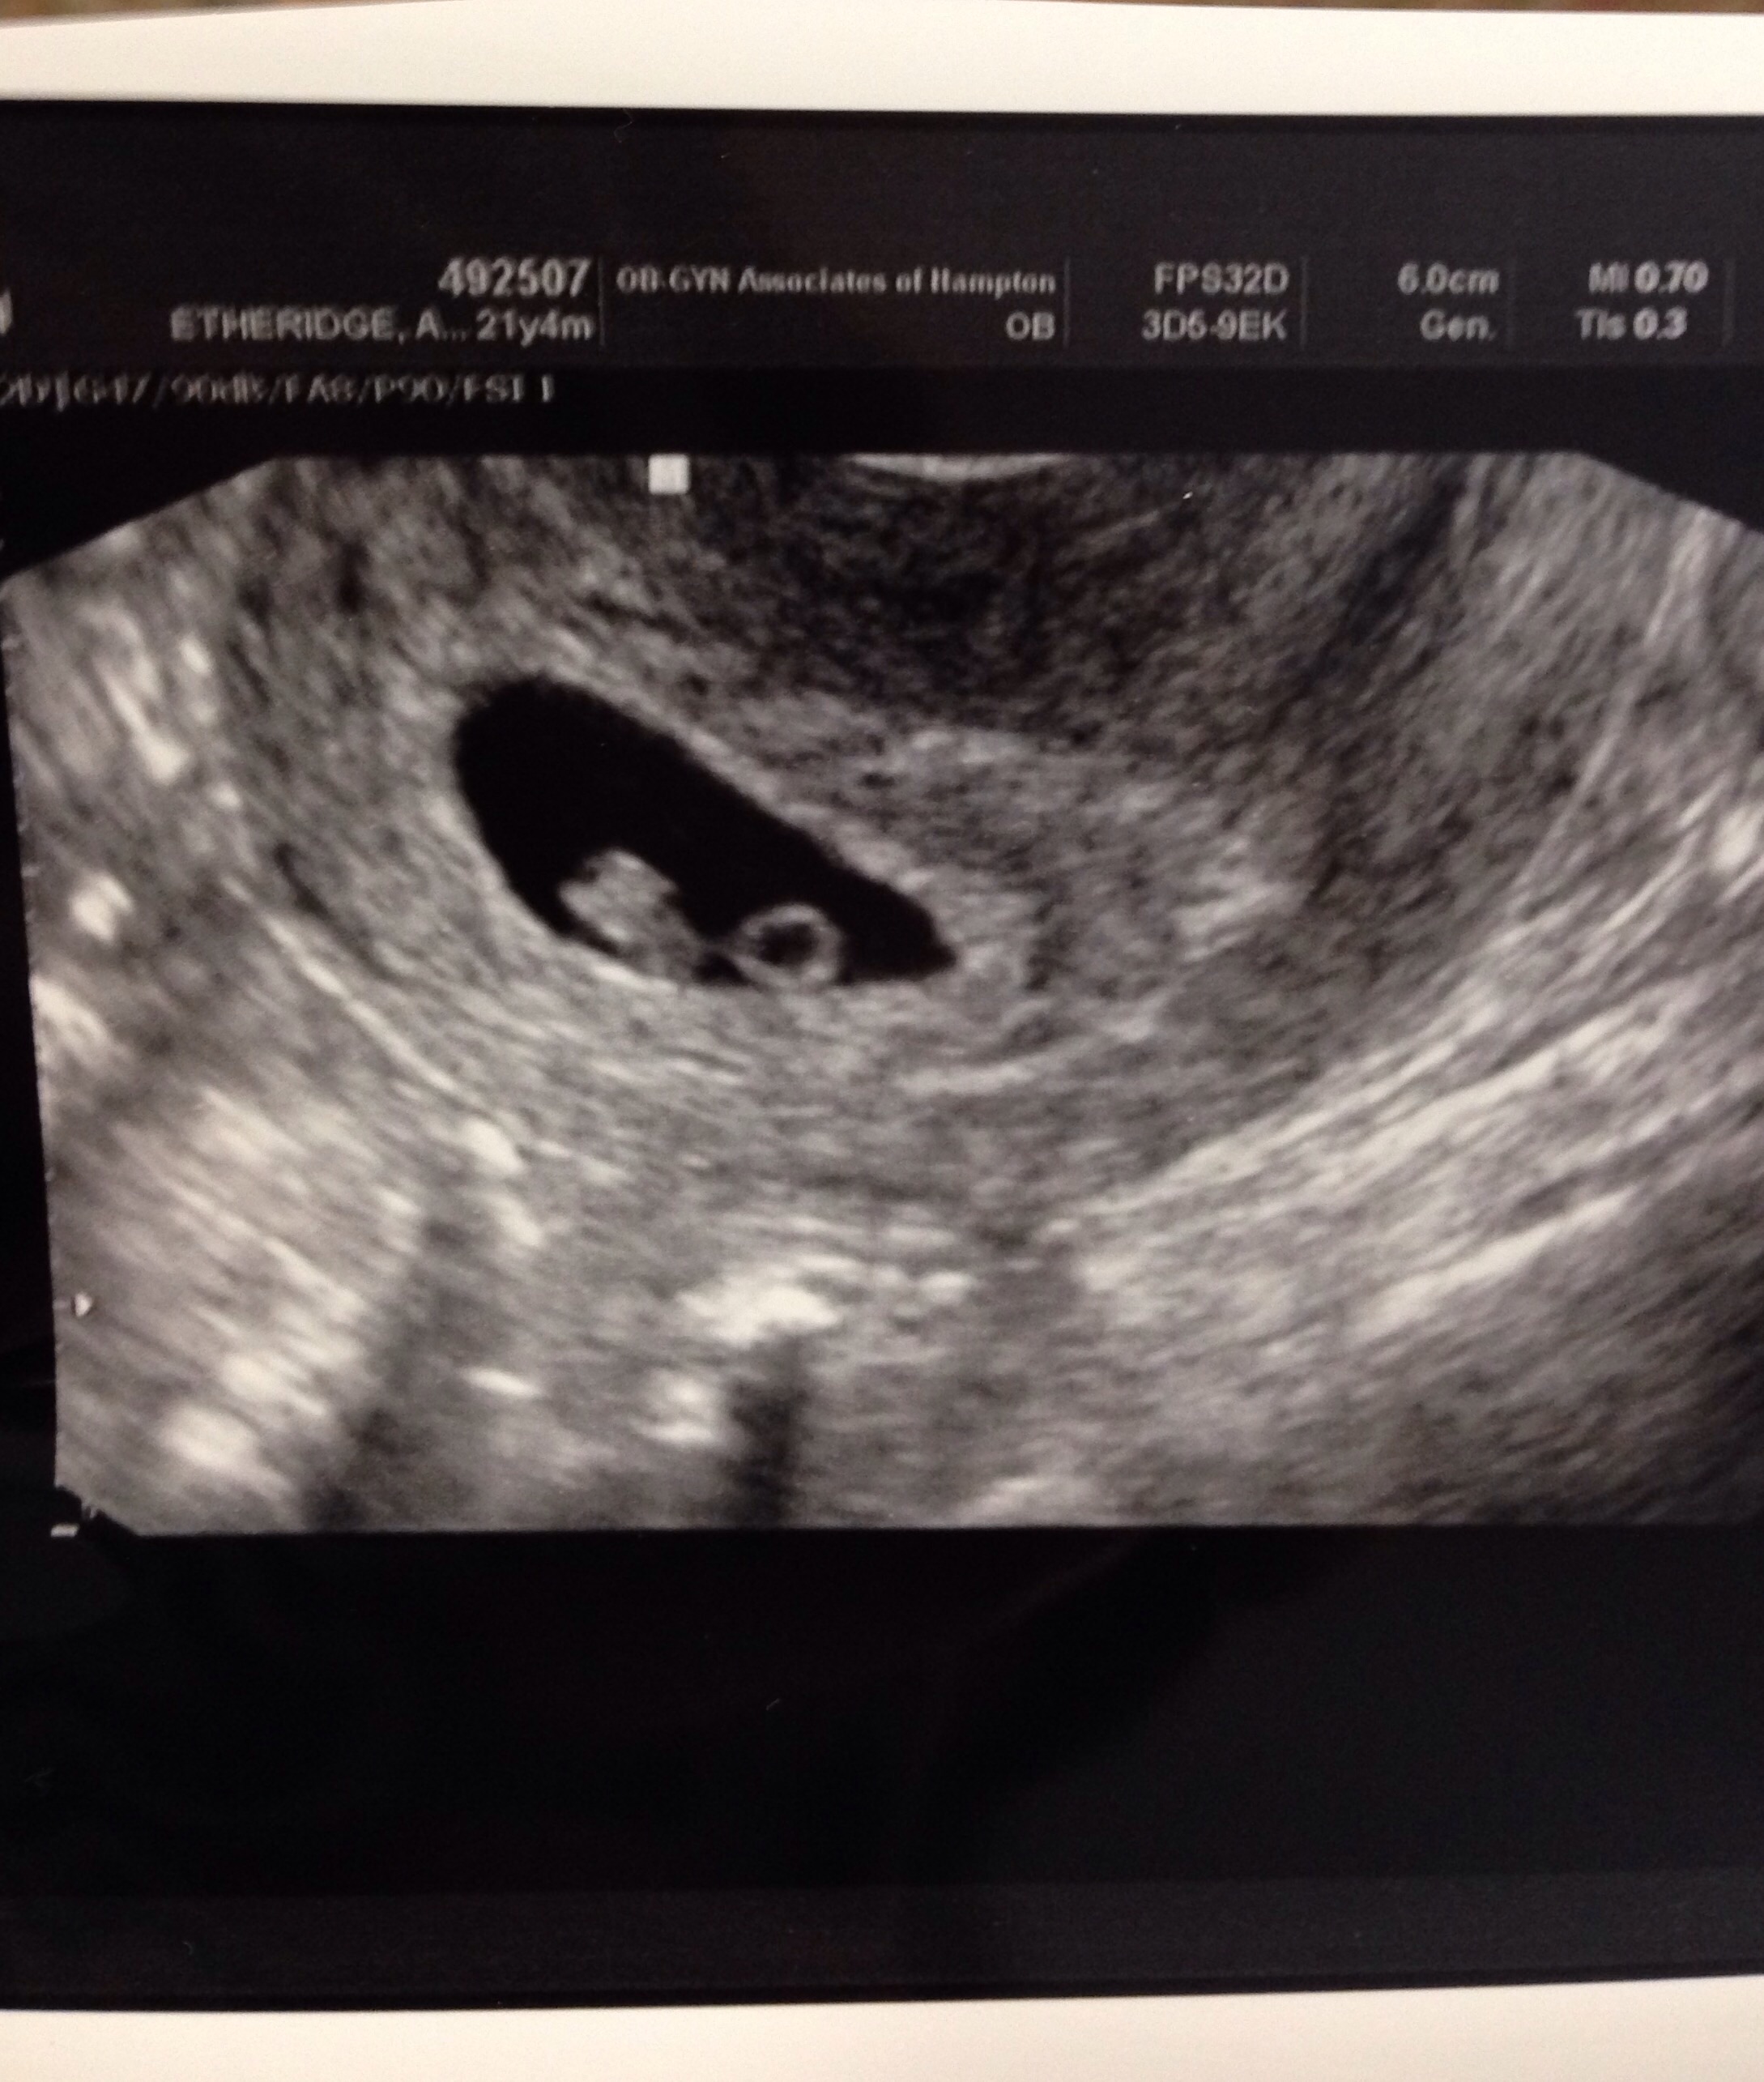

Personally it started as a confirmation ultrasound being done at a local "pregnancy center"; they do confirming ultrasounds for free and if need be work with you through your pregnancy. The results of that ultrasound raised a concern and I contacted my midwife who ordered blood work and a viability/dating ultrasound be done at the hospital. After the results of that which I posted above they have scheduled a follow up ultrasound in a few weeks to confirm viability again due to how early i am.